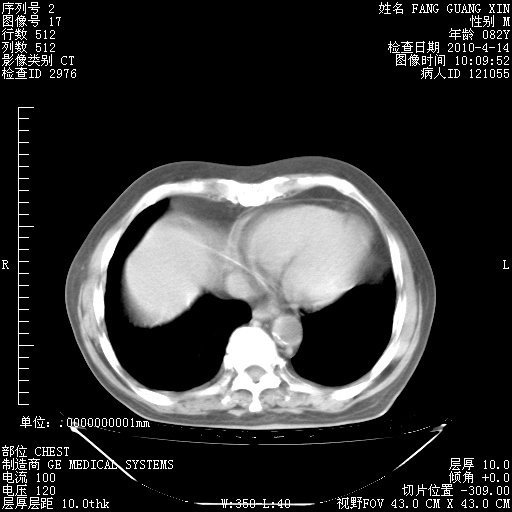

4月14日肺部CT

23.JPG

24.JPG

25.JPG

26.JPG

肺部CT平扫未见异常。